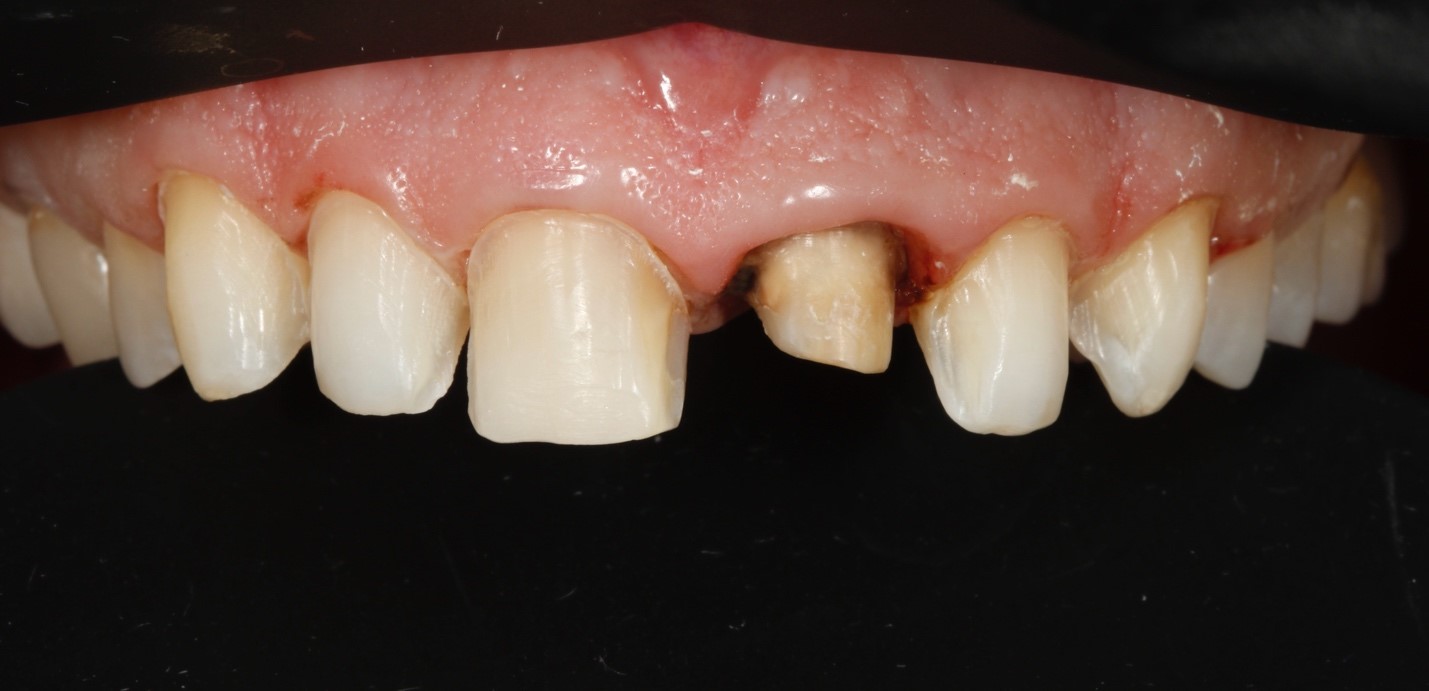

В третье посещение была проведена подготовка зубов под микроскопом под керамические реставрации. Изначала выполнена разметка зубов через временные реставрации, после чего был выполнен основной этап препарирования под контролем силиконовых ключей. Зуб 21 был подготовлен под коронку (Рисунок 3). Далее была проведена оценка цвета неподготовленный и подготовленных под керамические реставрации зубов (Рисунок 4). После снятия оттисков были изготовлены временные прямые реставрации Luxatemp A1 (DMG, Германия).

Рис. 3. Этапы препарирования зубов. А – разметка зубов через временные реставрации.

B – вид на этапе снятие оттисков.

С – проверка препарирования с помощью силиконового ключа.